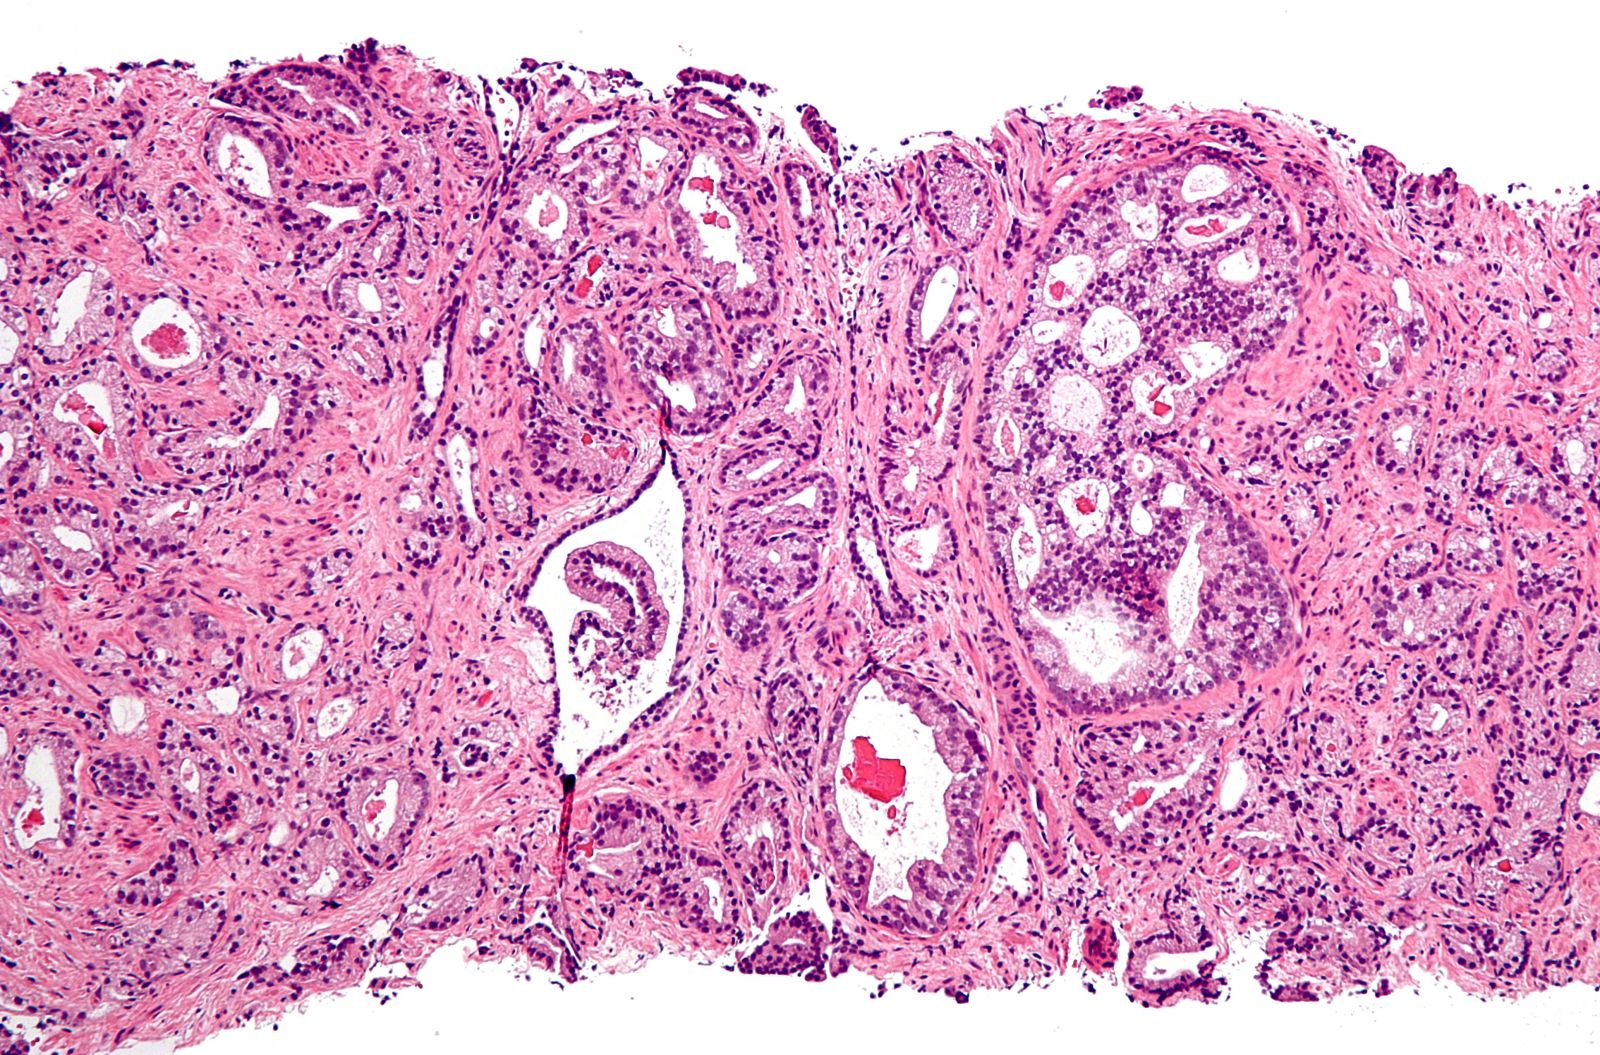

Đường có thể là chìa khóa để xét nghiệm ung thư tuyến tiền liệt sớm hơn, chính xác hơn

TNNN - Một loại xét nghiệm mới sử dụng đường để phát hiện ung thư tuyến tiền liệt sớm hơn và với độ chính xác cao hơn đang được phát triển bởi các nhà nghiên cứu tại Đại học Birmingham.

Thử nghiệm bằng cách xác định đường, được gọi là glycans trong máu. Những loại đường này được gắn vào các phân tử protein gọi là PSA và trải qua những thay đổi khác biệt khi tế bào ung thư có trong cơ thể. Các loại glycans đặc biệt có liên quan đến các loại ung thư khác nhau nhưng cho đến nay, không có công nghệ nào có sẵn để phát hiện glycans một cách chính xác, kịp thời và đủ cụ thể.

Nghiên cứu do một nhóm trong Khoa Kỹ thuật Hóa học của Đại học Birmingham dẫn đầu, đã phát triển một kỹ thuật có thể xác định glycans liên quan đến ung thư với độ chính xác chưa từng có.

Một xét nghiệm mới về ung thư tuyến tiền liệt là rất cần thiết bởi vì các xét nghiệm hiện tại chỉ có thể đưa ra dấu hiệu tăng PSA trong mẫu máu. Điều này có thể cho kết quả dương tính giả trong khoảng 50% trường hợp, là do mức PSA của một người đàn ông có thể tăng lên vì một số lý do khác nhau, không nhất thiết liên quan đến ung thư. Ngoài ra, khoảng 25% nam giới bị ung thư tuyến tiền liệt không có PSA tăng cao, vì vậy xét nghiệm không chẩn đoán được những bệnh nhân này.